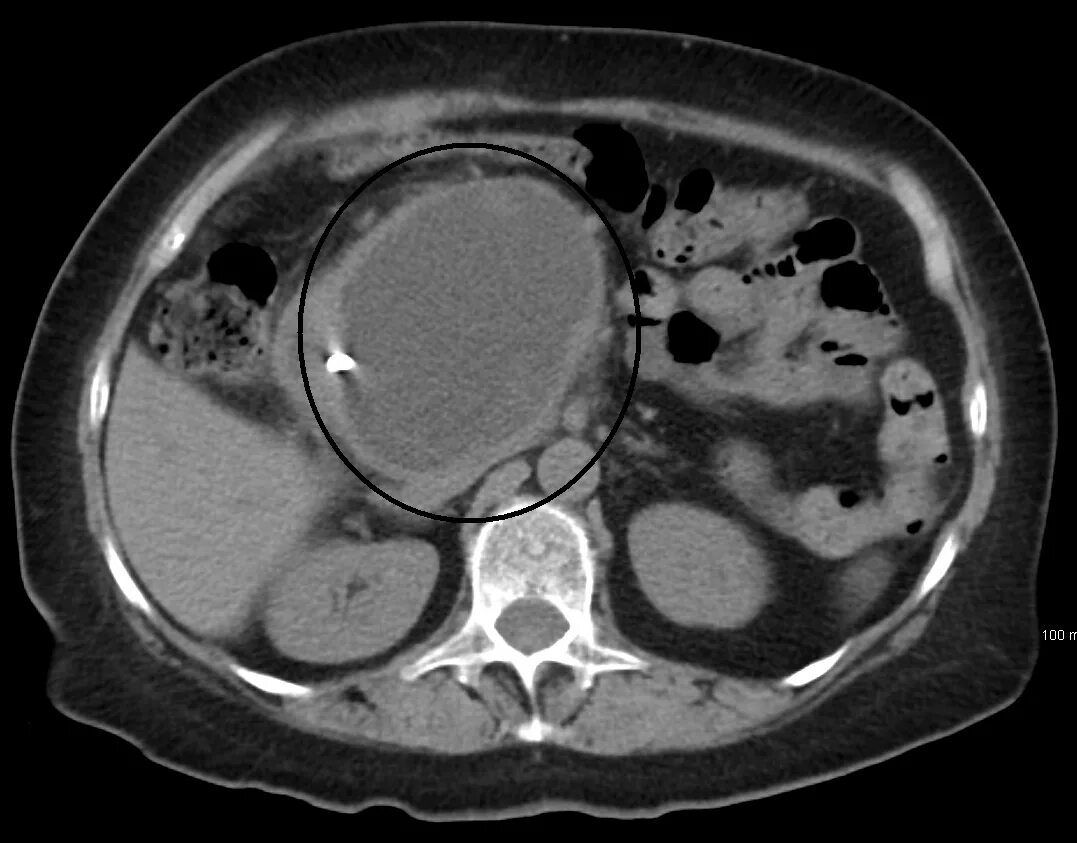

Мрт кисты поджелудочной